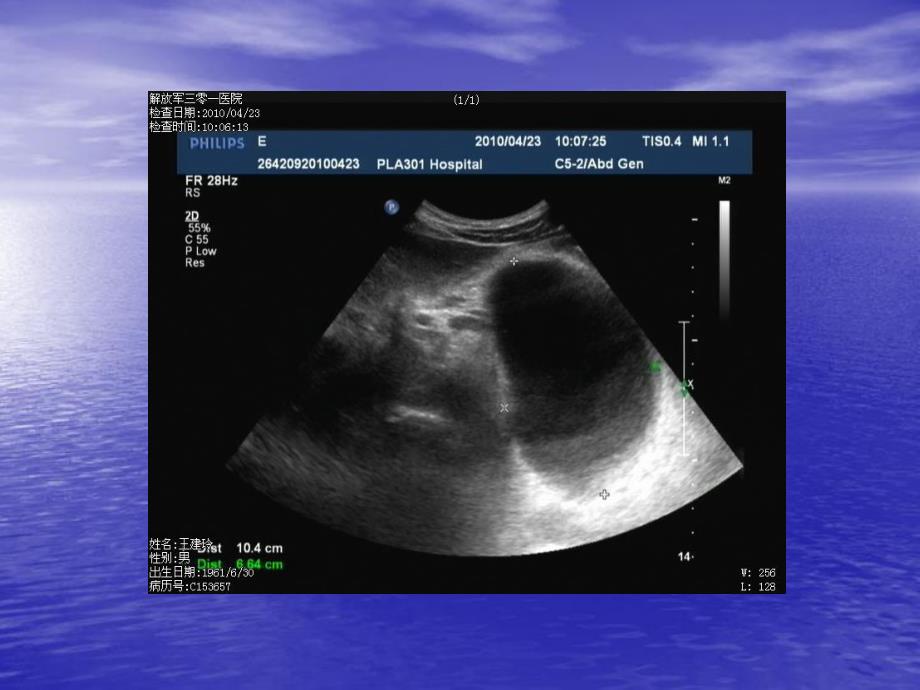

胰腺假性囊肿 患者,男,患者,男,28岁,一个月前岁,一个月前因急性胰腺炎住院治疗,当时血、因急性胰腺炎住院治疗,当时血、尿淀粉酶、脂肪酶、中性粒细胞尿淀粉酶、脂肪酶、中性粒细胞均升高。入院后经禁食、补液、均升高。入院后经禁食、补液、抗炎治疗后症状缓解。此次门诊抗炎治疗后症状缓解。此次门诊复查。目前尚存在间断上腹部胀复查。目前尚存在间断上腹部胀痛,每日大便痛,每日大便2-3次。次。(中重度脂肪肝,胰腺假性囊肿,(中重度脂肪肝,胰腺假性囊肿,直径约直径约1.7cm)诊断:胰腺假性囊肿病因约约20%病例发生在胰腺外伤后;病例发生在胰腺外伤后;5%病例由肿瘤所致。病例由肿瘤所致。少数假性囊肿无症状。大多数病例临床症少数假性囊肿无症状。大多数病例临床症状系囊肿压迫邻近脏器和组织所致。如上状系囊肿压迫邻近脏器和组织所致。如上腹部疼痛、腹胀,恶心、呕吐,食欲下降、腹部疼痛、腹胀,恶心、呕吐,食欲下降、体重减轻、低热等症状;部分患者上腹部体重减轻、低热等症状;部分患者上腹部可扪及包块。可扪及包块。急性胰腺炎的病因(国内)胆道疾患酗酒饮食因素高脂血症乳头括约肌功能紊乱该病发病率不断攀升生活水平提高饮食结构改变诊断水平提高诊断及鉴别诊断诊断及鉴别诊断